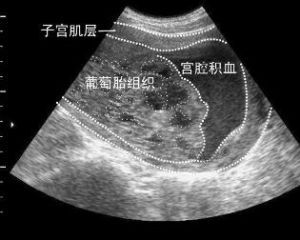

4 分泌物觀察 宮口未開的產婦行剖宮產術後,因宮腔積血出現凝血塊堵住宮口而無陰道流血,或經陰道流出一種淡紅色或淡黃色分泌物,此時要注意宮腔積血的其他徵象。

宮腔積血6 術後注意情況 術後2h內一定要嚴密觀察,並不時按摩宮體,壓出宮腔內積血,促進子宮收縮。